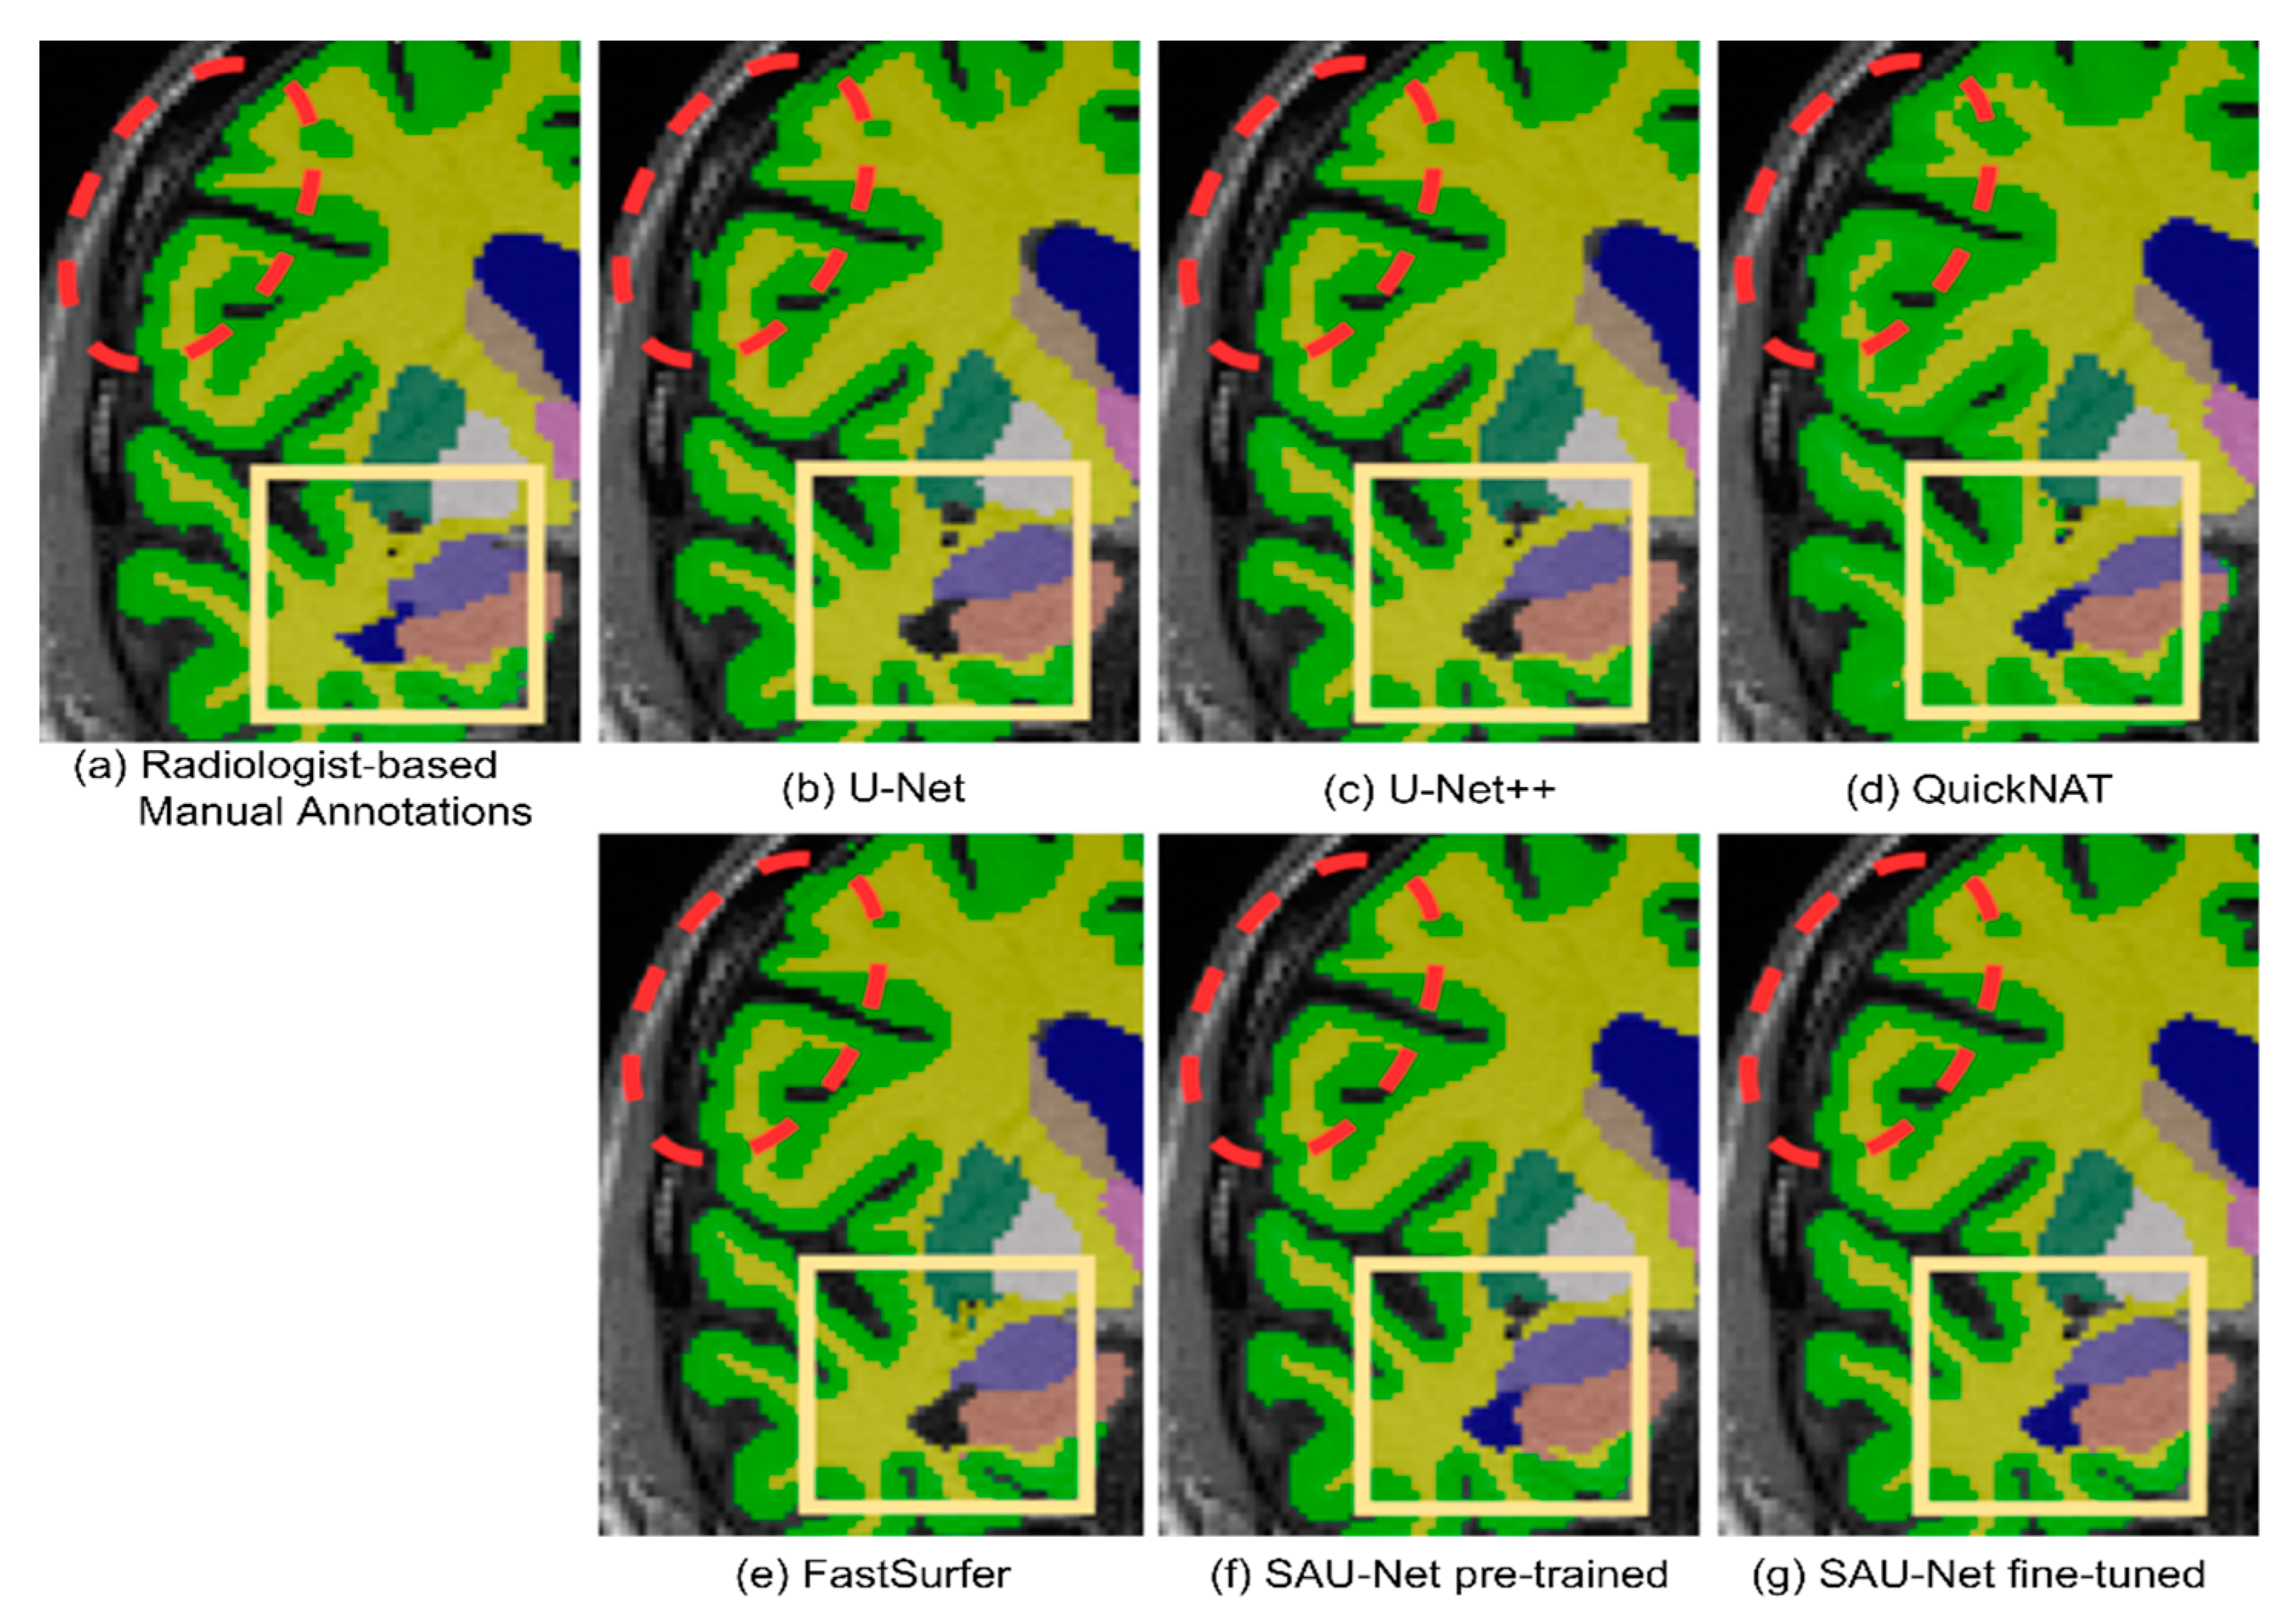

3.1.2. Qualitative Analysis